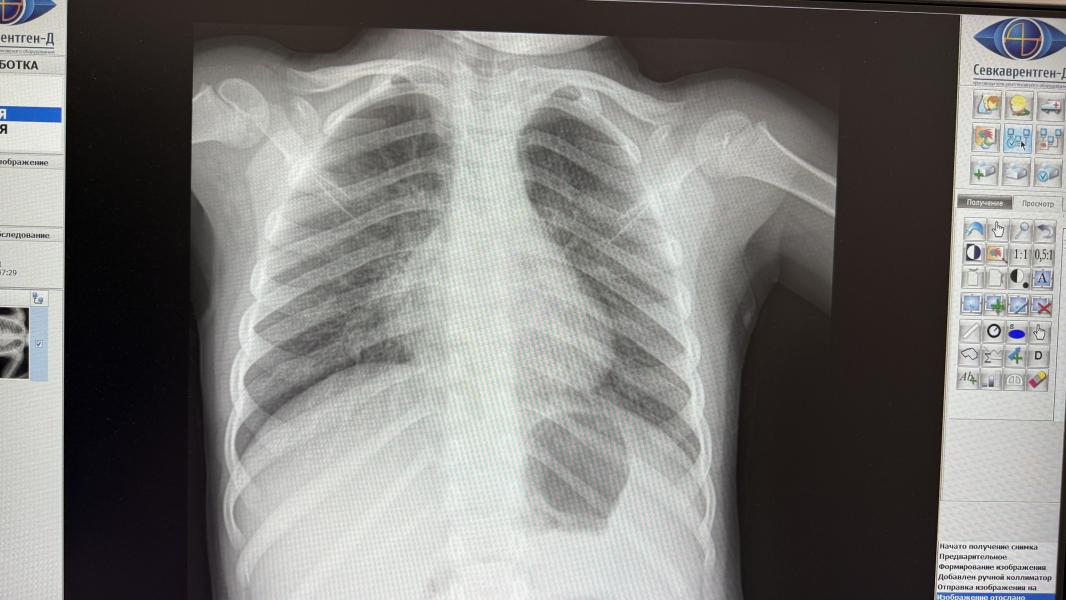

Девочки, у дочери температура уже несколько дней, кашель уже на протяжении 2-3 месяцев (не коклюш). Поехали во вторую детскую, там послушали ее, сказали все нормально, по моей просьбе сделали рентген. Проверили на моем телефоне и сказали за секунду «чисто» и все. Отправили домой. Больше никакой проверки, никакой рекомендации. Не знаю что нужно делать, чтобы некоторые врачи осмотрели как следует ребенка. Я не про всех, бывают такие странные. «Зачем вы вообще вечером приехали? Это не серьезный слу...